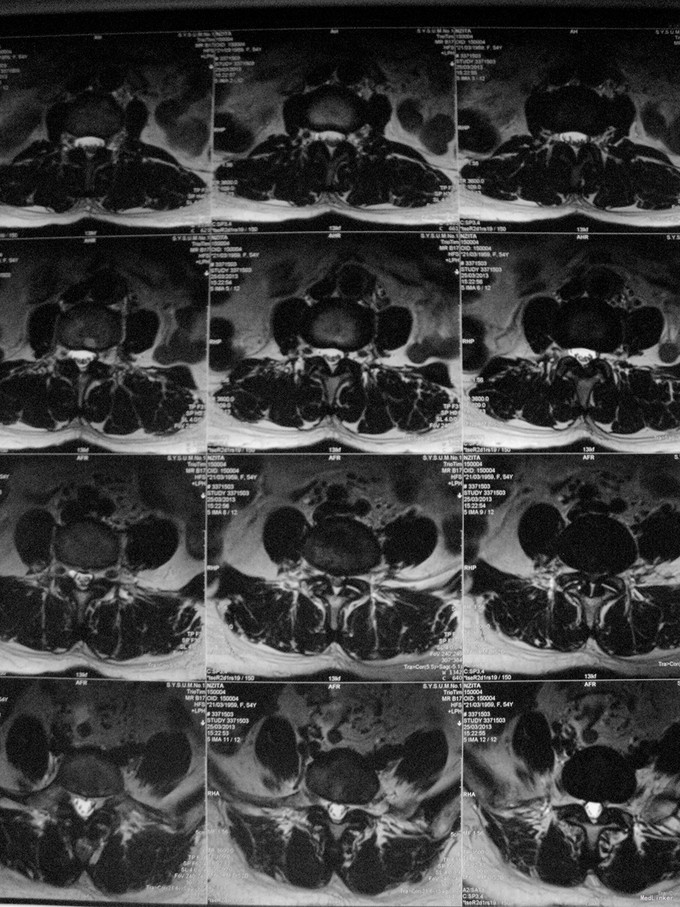

查体:脊柱生理弯曲存在,腰椎活动受限,L4/L5棘突压痛叩痛,叩击痛。双侧直腿抬高试验(-)。双下肢皮肤感觉正常,双侧髂腰肌、股四头肌、双侧胫前肌、踇背伸肌肌力Ⅳ级,腹壁反射、肛门反射正常,两侧膝正常,双侧踝反射未引出。双侧Babinski征(-),双侧皮温及色泽正常,双侧足背动脉搏动良好。 辅助检查:X光片示:动力位片显示腰椎4/5椎间失稳。MRI检查显示:腰4/5椎间盘突出,黄韧带肥厚致椎管狭窄,相应节段硬膜囊受压改变。

诊断:腰4/5椎管狭窄并失稳症。 治疗:给予行后路腰4/5右侧椎板间开窗减压椎间盘摘除并肥厚黄韧带切除+棘突间wallis固定术。